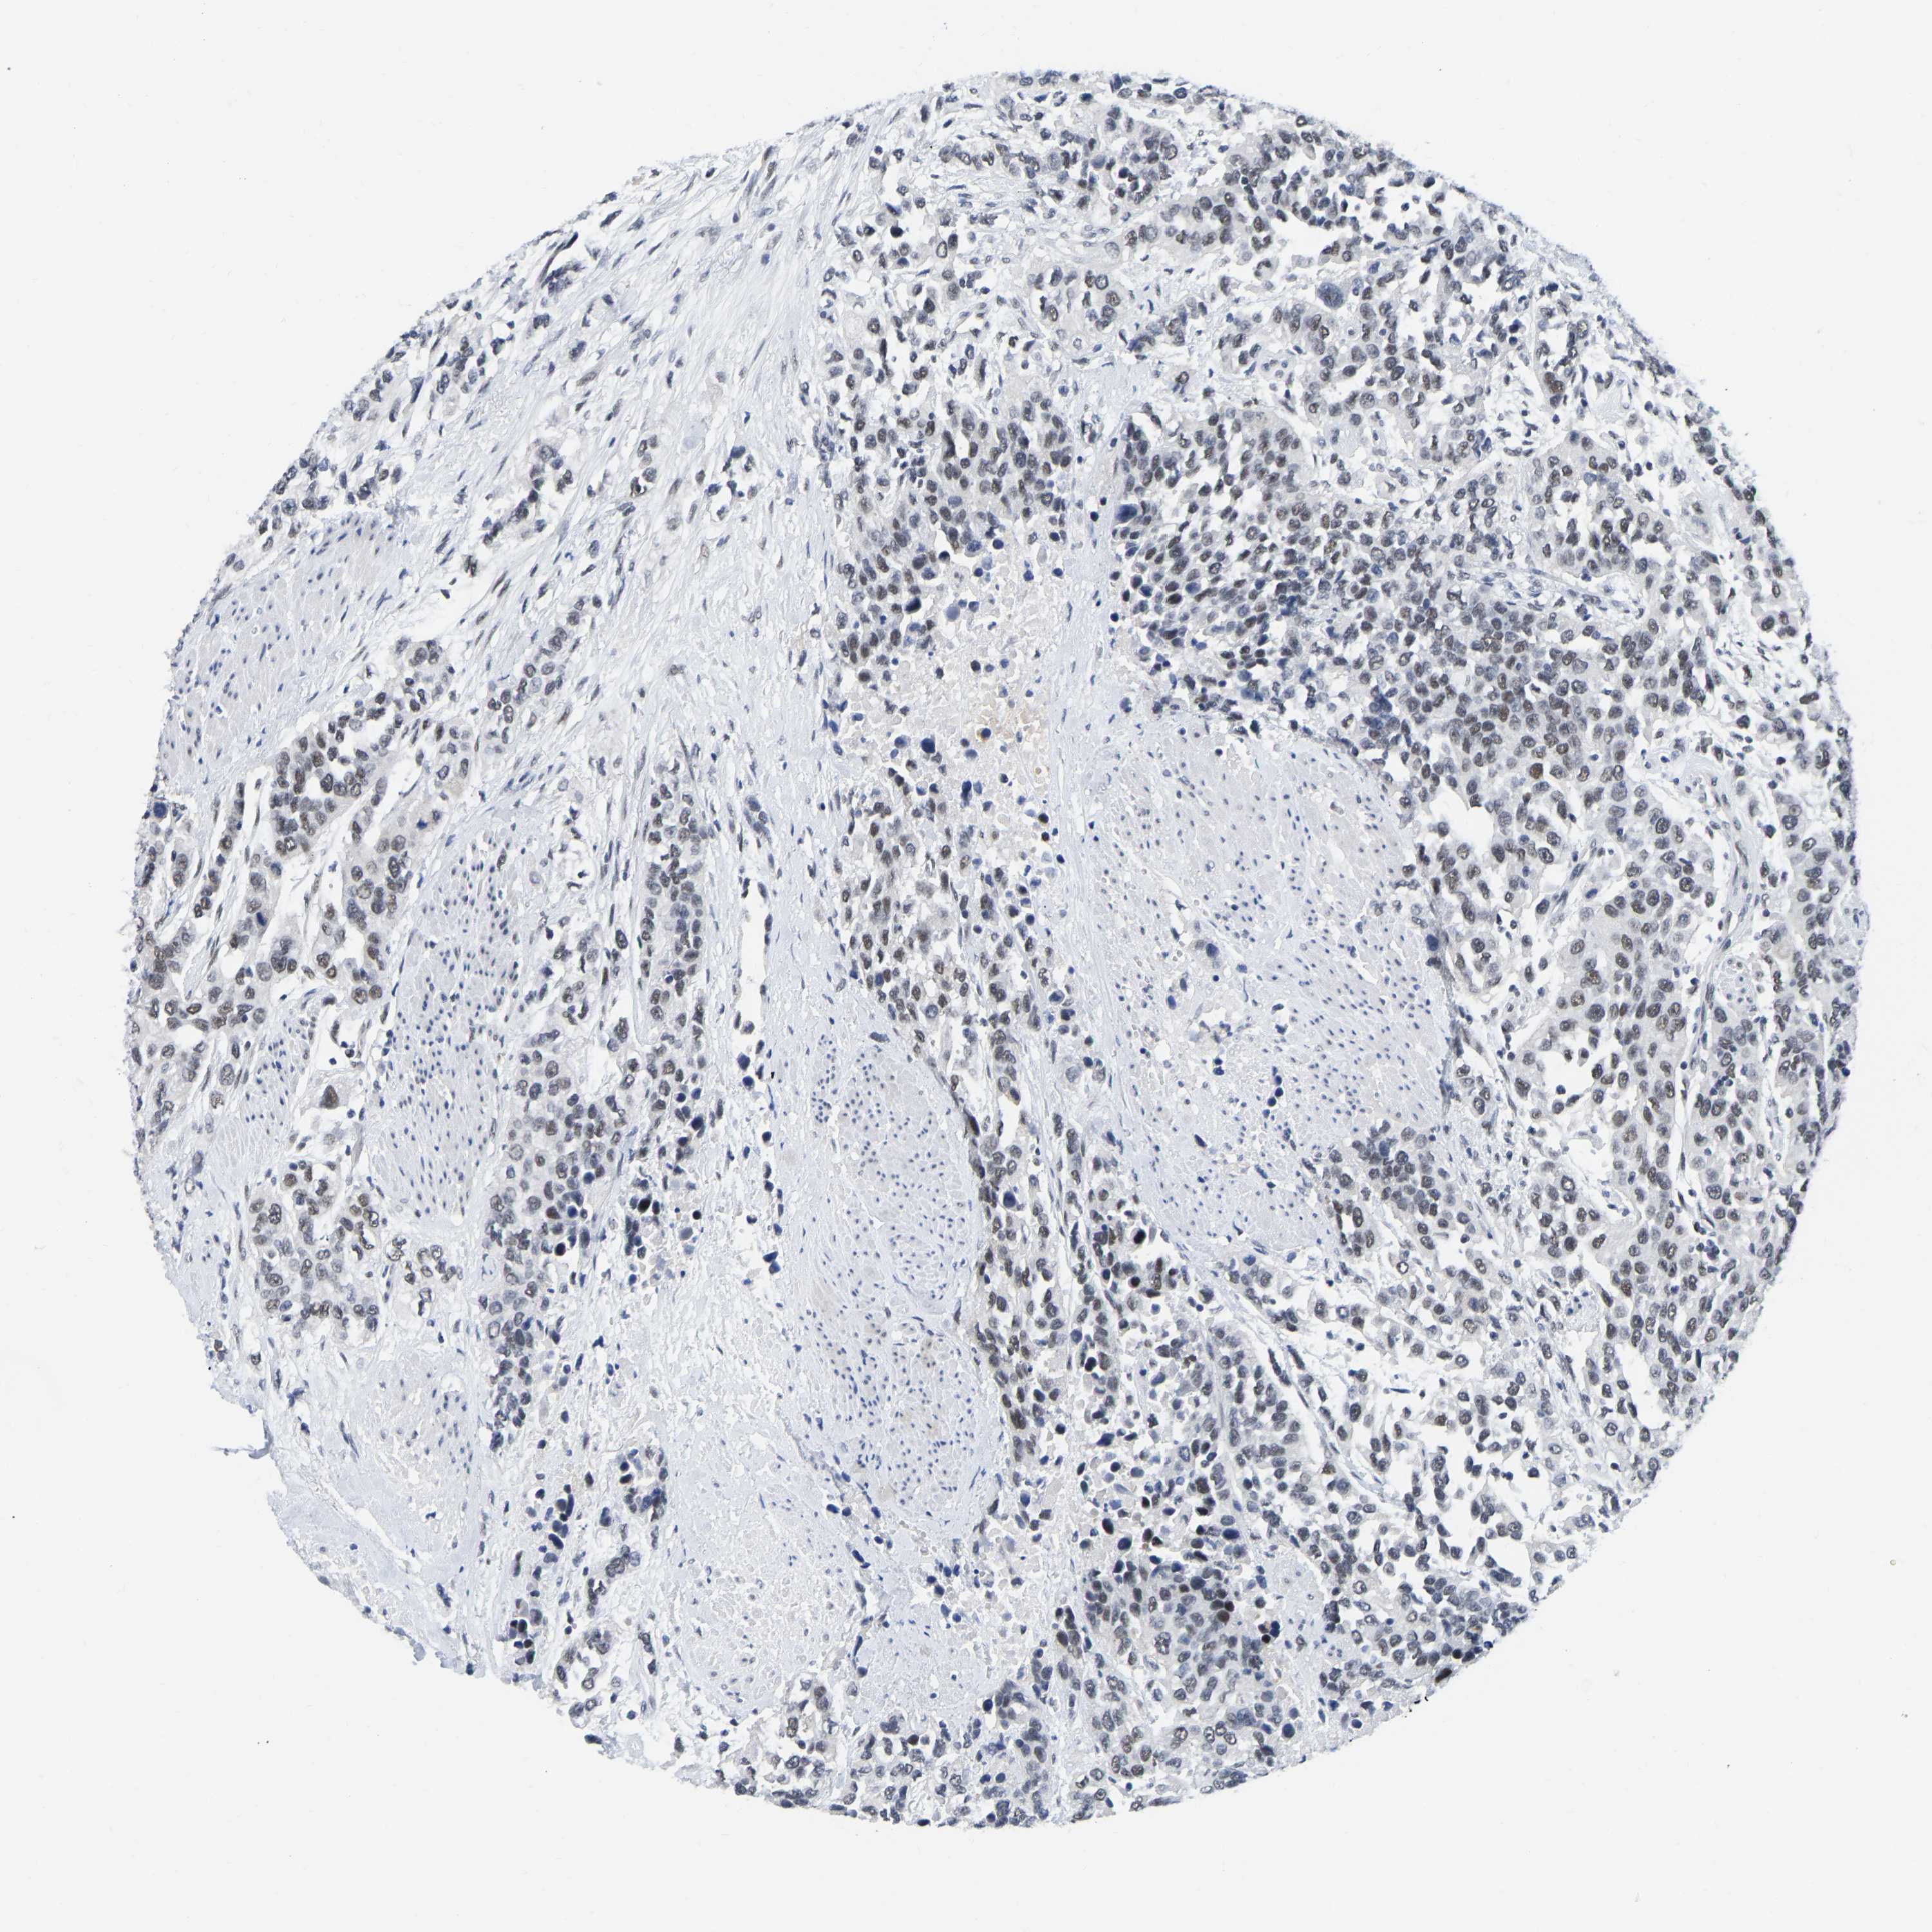

UROTHELIAL CANCER - Protein expressioni

A mouse-over function shows sample information and annotation data. Click on an image to view it in a full screen mode. Samples can be filtered based on level of antibody staining by selecting one or several of the following categories: high, medium, low and not detected. The assay and annotation is described here.

Antibody stainingi

Antibody staining in the annotated cell types in the current human tissue is reported as not detected, low, medium, or high, based on conventional immunohistochemistry profiling in selected tissues. This score is based on the combination of the staining intensity and fraction of stained cells.

Each image is clickable and will lead to virtual microscopy that enables deeper exploration of all samples and also displays staining intensity scores, fraction scores and subcellular localization as well as patient and tissue information for each sample.

Antibody CAB019416

Staining

High

Medium

Low

Not detected

Intensity

Strong

Moderate

Weak

Negative

Quantity

>75%

75%-25%

<25%

None

Location

Nuclear

Cytoplasmic/membranous

Cytoplasmic/membranous,nuclear

Urothelial carcinoma, Low grade

Urothelial carcinoma, High grade